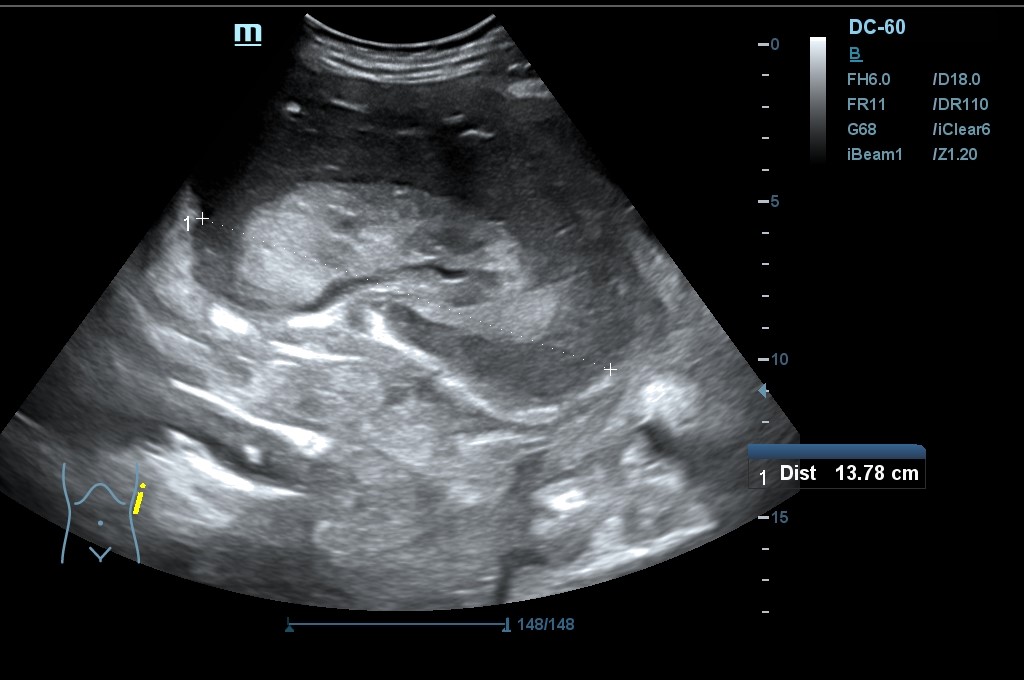

Hallazgo de lo que impresiona de nefromegalia izquierda de aproximadamente 14 cm con hidronefrosis bilateral grado 2.

Tras la segunda ecografía se deriva a la paciente a la Unidad de Diagnóstico Rápido de Medicina Interna donde ingresa para completar estudio. Tras ecografía en la que informan de extenso tejido hipoecoico periaórtico y perirrenal izq. (nefromegalia izq.) con extensión nodular al mesenterio, se establece la sospecha de síndrome linfoproliferativo, así como en un TC posterior y que se confirma como Linfoma No Hodgkin mediante biopsia.